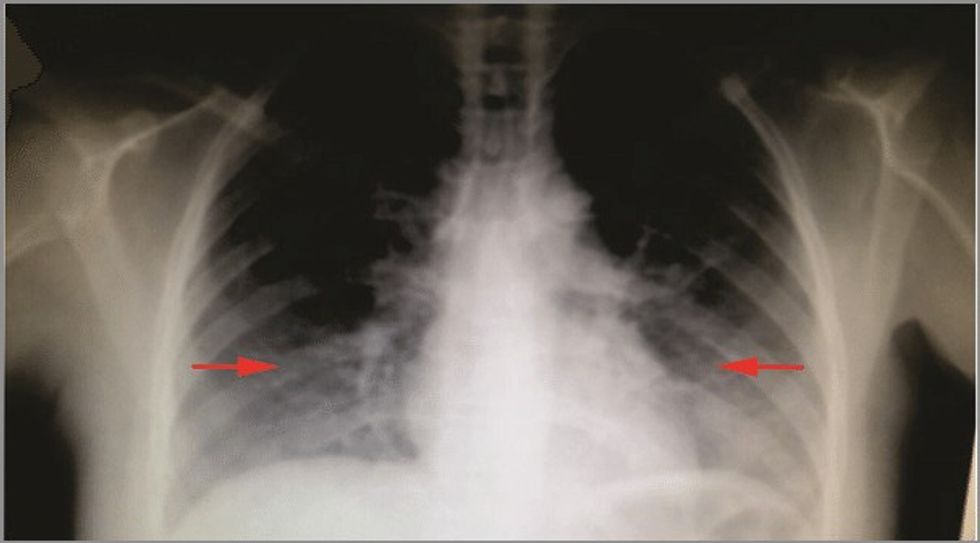

De Rossi do ta vazhdojë periudhën e shërimit në shtëpi, duke qenë se arsyeja e shtrirjes në spital ka qenë pneumonia bilaterale intersticiale si pasojë e infeksionit me COVID-19.

Pneumonia bilaterale intersticiale është një infeksion serioz që mund të shkaktojë inflamacion dhe cikatrizime në mushkëri.

Është një nga format e shumta të sëmundjeve intersticiale të mushkërive që përfshin indin përreth qeskave të vogla të ajrit (alveole) të mushkërive tuaja.

Këtë lloj pneumonie mund ta zhvilloni si pasojë e COVID-19. Format bilaterale të pneumonisë i përfshijnë të dy mushkëritë.